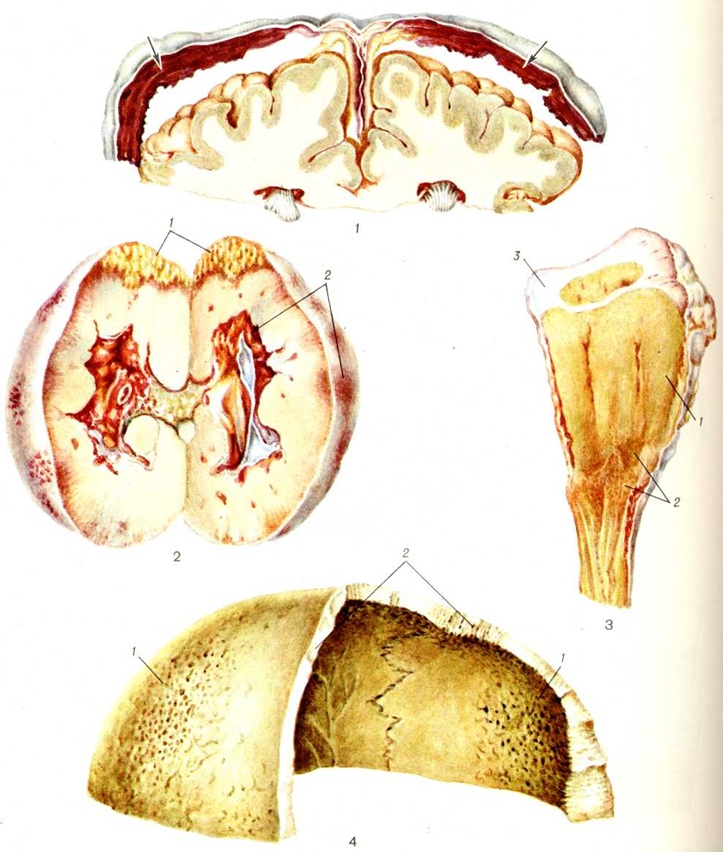

Мраморная болезньМраморная болезнь [синонимы: болезнь Альберс-Шенберга, врождённый семейный остеосклероз, семейная окаменелость костей, генерализованный ломкий (хрупкий) остеосклероз] — редко встречающееся врождённое заболевание диспластического характера, проявляющееся диффузным остеосклерозом большинства костей скелета. Мраморная болезнь впервые описана на основании рентгенологическое картины Альберс Шенбергом (Н. Е. Albers-Schonberg) в 1904 и 1907 годы и носит его имя. В СССР первые работы, посвящённые Мраморная болезнь, опубликованы в 1929—1930 годы М. Б. Копыловым, М. Ф. Руновой, Н. М. Кудрявцевой. Публикации, как правило, носят описательный характер и не раскрывают существа заболевания, которое остаётся невыясненным. Мраморная болезнь встречается во всех возрастных группах. Она распространена одинаково на всех континентах, в равной степени среди мужчин и женщин . Этиология неизвестна. В подавляющем большинстве случаев Мраморная болезнь носит семейный характер и передаётся из поколения в поколение, хотя в литературе неоднократно описана спорадически возникавшая Мраморная болезнь у людей с неотягощённой наследственностью. Патогенез мало изучен. М. В. Волков относит её к заболеваниям диспластического характера, то есть к врождённым аномалиям развития, в основе которых лежат патологический разрастания кости, вытесняющие кроветворную ткань. А. В. Русаков ставит Мраморная болезнь в один ряд с остеомиелодисплазией, хотя связь между ними не совсем ясна. Герстель (Gerstel) рассматривает Мраморная болезнь как результат нарушения взаимодействия трёх различных функциональный частей скелета: опорного, эндостального и кроветворного аппаратов. Нарушение координации между ними приводит, по мнению А. В. Русакова, к порочному формированию скелетогенной ткани и к недостаточности миелогенной ткани. Дисплазия скелетогенной мезенхимы выражается в образовании функционально неполноценной кости с накоплением в костной системе избыточного количества обызвествлённого, очень непрочного, легко ломающегося костного вещества. Миелогенная ткань развивается в недостаточном количестве. Деление Мраморная болезнь на доброкачественную и злокачественную формы определяется степенью вовлечения того или иного производного первичной мезенхимы. Когда преобладает поражение только скелетогенной мезенхимы, говорят о доброкачественном варианте Мраморная болезнь, который протекает только с остеосклерозом и часто длительное время не даёт никаких клинические, проявлений. Если же в процесс вовлекается и миелогенная мезенхима, то развивается тяжёлая анемия — злокачественный вариант течения мраморной болезни, при котором рано проявляются клинические, симптомы. Патологическая анатомия. Основные изменения при Мраморная болезнь локализуются в костной ткани и носят универсальный характер. Кости при Мраморная болезнь очень тяжёлые, с трудом распиливаются, но легко раскалываются. Весьма типичным является вид бедренных и плечевых костей, имеющих булавовидные утолщения соответственно в нижней и верхней третях, возникающие вследствие более бурного костеобразования в этих участках. На распиле длинные трубчатые кости не имеют костномозговой полости; вместо неё видно компактное вещество, заменяющее губчатое вещество и плоских костей (позвоночника, ключиц, костей черепа). Иногда в длинных трубчатых костях компактное вещество может чередоваться с участками, состоящими из более порозного костного вещества, которое имеет вид серовато-красноватого кольца или пояса, идущего поперёк длинника кости (цветной рисунок 1). Пояс разрежения вещества кости указывает на приостановку процессов избыточного костеобразования на определённом этапе болезни. Макроскопически удаётся обнаружить изменения со стороны коркового вещества как длинных трубчатых, так и плоских костей. Местами непрерывность коркового вещества нарушается и в нем вместо компактного обнаруживается губчатое строение. Вследствие такой своеобразной перестройки поверхность кости перестаёт быть гладкой, приобретая шероховатый, губчатый вид (цветной рисунок 2). Корковое вещество кости имеет характер плотной (компактной) кости или превращается в губчатую кость с костномозговыми пространствами, содержащими преимущественно незрелую кроветворную ткань (так называемый медуллизация коркового вещества). Медуллизация представляет собой компенсаторное явление в ответ на исчезновение костномозговых пространств. В костях черепа медуллизация может служить источником эпидуральных, а иногда и субдуральных кровоизлияний (цветной рисунок 3). |